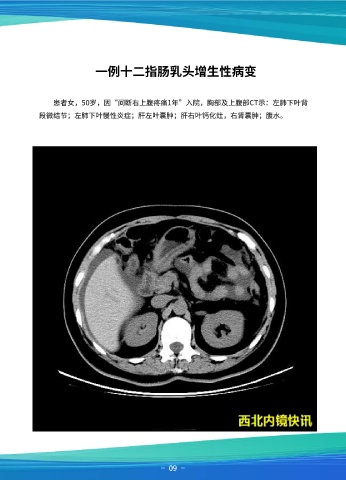

一例十二指肠乳头增生性病变

患者女,50岁,因“间断右上腹疼痛1年”入院,胸部及上腹部CT示:左肺下叶背

段微结节;左肺下叶慢性炎症;肝左叶囊肿;肝右叶钙化灶,右肾囊肿;腹水。